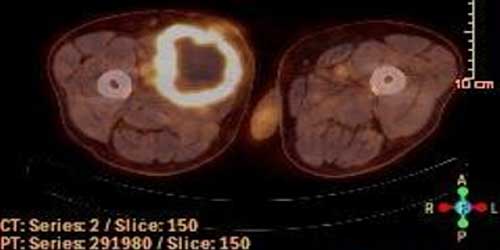

Liposarkom

Kötü huylu yumuşak doku tümörleri arasında ikinci sıklıktadır. Nedeni tam olarak bilinmemektedir. Çok farklı yaşlarda görülebilir fakat sıklıkla 40 yaş sonrası ortaya çıkar.